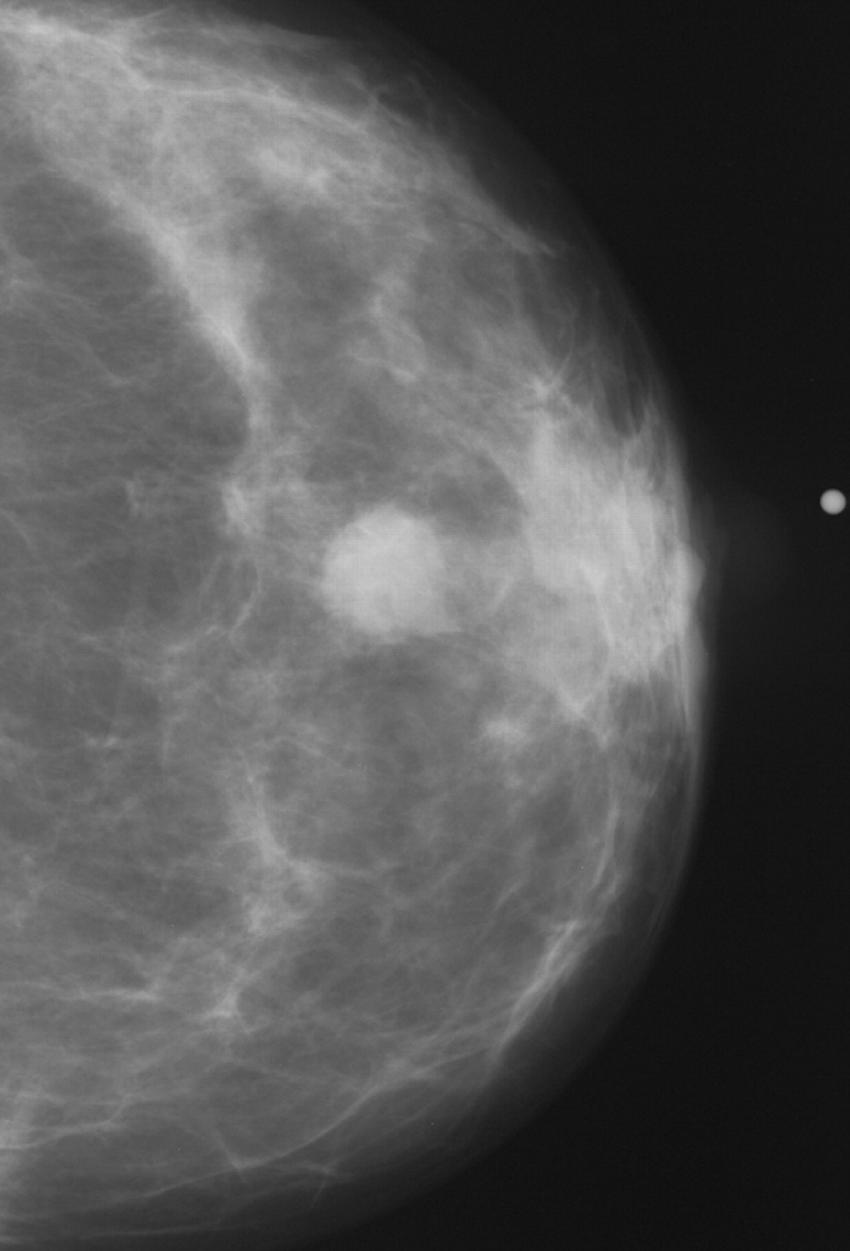

Figure 2. Normal mammogram.